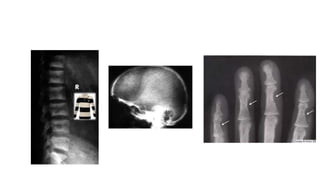

Xray findings

• Early findings consist of generalized deossification.

• The trabeculae become thinned out and disappear and cortices are

narrowed

• As disease progresses, cysts appear throughout skeleton, bending

deformities develop and renal calculi are observed.

• Skull displays diffuse osteoporosis – ‘Pinhead Stippling’

• Vertebrae are porotic and deeply indented by ballooned discs.

Collapse is frequent. ‘Rugger Jersey spine’

• Dental films reveal dimineralization of mandible and disappearance of

lamina dura and epulis tumors

Xray findings • Earlyfindings consist of generalized deossification. • The trabeculae become thinned out and disappear and cortices are narrowed • As disease progresses, cysts appear throughout skeleton, bending deformities develop and renal calculi are observed. • Skull displays diffuse osteoporosis – ‘Pinhead Stippling’ • Vertebrae are porotic and deeply indented by ballooned discs. Collapse is frequent. ‘Rugger Jersey spine’ • Dental films reveal dimineralization of mandible and disappearance of lamina dura and epulis tumors